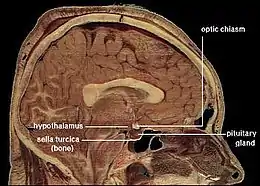

The corpus callosum forms the floor of the longitudinal fissure that separates the two cerebral hemispheres. Part of the corpus callosum forms the roof of the lateral ventricles.[5]

The front part of the corpus callosum, towards the frontal lobes, is called the genu ("knee"). The genu curves downward and backward in front of the septum pellucidum, diminishing greatly in thickness. The lower, much thinner part is the rostrum and is connected below with the lamina terminalis, which stretches from the interventricular foramina to the recess at the base of the optic stalk. The rostrum is named for its resemblance to a bird's beak.

The callosal sulcus separates the corpus callosum from the cingulate gyrus.

The anterior cerebral arteries are in contact with the undersurface of the rostrum; they arch over the front of the genu and are carried along the trunk, supplying the front four-fifths of the corpus callosum.[7]